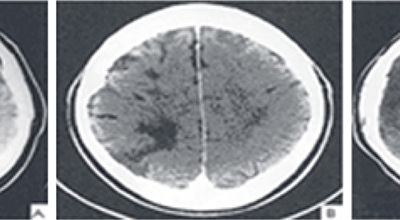

뇌경색 후유증

뇌경색 후유증은 올바르게 걷지 못하고, 말을 잘 못하거나, 나의 의지와는 다르게 생기는 문제점들이 일어날 있답니다. 뇌경색이 오면 후유증이 남는 것이 기본이며 일주일 안으로 나타나게 될 수 있다고 하네요. 이 기간이 지나도 예후가 없다면 서서히 회복이 되는 과정에 있다고 생각하시면 되어요.

뇌경색 후유증은 3개월에서 6개월 사이에 서서히 회복 될 수 있답니다. 치료가 늦어져서 뇌경색 후유증이 심각하게 자리잡게 된다면 일상생활이 어려울 정도로 육체에 이상이 있는 상태가 유지될 수 있답니다.